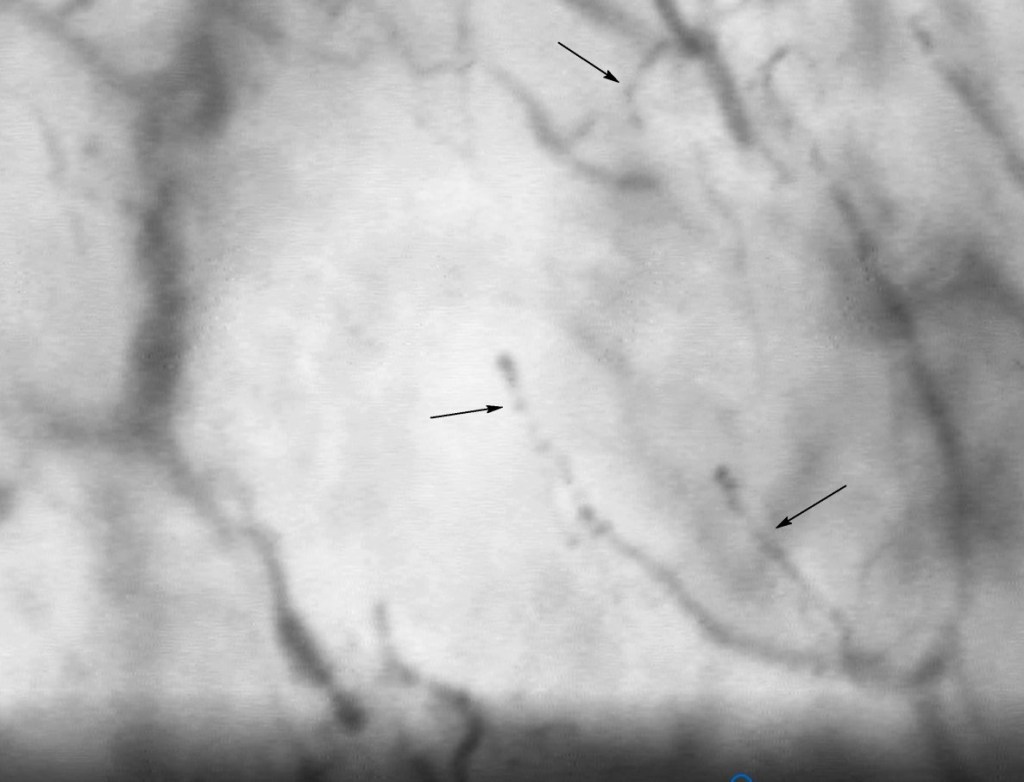

Microscopic image of sublingual blood vessels. The arrows point to erythrocytes (red blood cells) when passing through the microcirculation, where properties such as aggregation (when they are “stuck”) and deformability (when they become more rigid) interfere with blood viscosity.